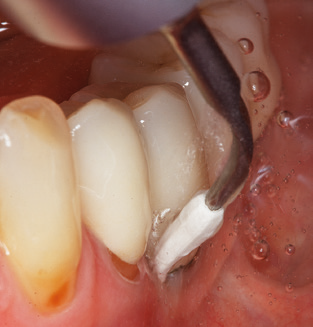

Die gute Ausleuchtung des Arbeitsfeldes stellt eine wesentliche Erleichterung dar. Bei dem von den Autoren genutzten System ist dies gelungen, indem ein 5facher LEDRing in das Handstück integriert wurde. Natürlich werden für dieses System unterschiedliche Arbeitsspitzen für die jeweiligen Indikationsbereiche angeboten. Eine gerade, universell einsetzbare Spitze ist das Basisinstrument zur maschinellen Instrumentierung natürlicher Zähne (Abb. 5a und b). Für schwer zugängliche Bereiche im Seitenzahnbereich werden gebogene Spitzen angeboten, die auch einen Zugang zu freiliegenden Furkationen ermöglichen (Abb. 6).

Unerlässlich für die UPT implantat prothetisch versorgter Patienten sind natürlich Arbeitsspitzen für die Reinigung von Implantatoberflächen. Der Implantatreinigungsaufsatz des hier verwendeten Systems zeichnet sich dabei durch eine spitz zulaufende sechskantige konische Form aus. Dieses Design erlaubt ein leichtes atraumatisches Eindringen in die periimplantäre Tasche und zeigt eine gute Reinigungsleistung (Abb. 7).